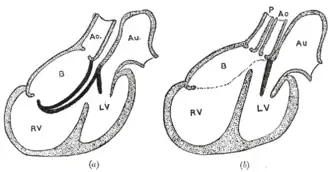

Additional images

Diagrams to illustrate the transformation of the bulbus cordis. Ao. Truncus arteriosus. Au. Atrium. B. Bulbus cordis. RV. Right ventricle. LV. Left ventricle. P. Pulmonary artery.

Diagrams to illustrate the transformation of the bulbus cordis. Ao. Truncus arteriosus. Au. Atrium. B. Bulbus cordis. RV. Right ventricle. LV. Left ventricle. P. Pulmonary artery.